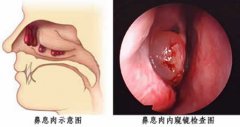

鼻息肉是有什么原因引起的

鼻息肉属于鼻部的一种常见疾病,鼻息肉对患者的生活、工作都有的影响,降低了患者的生活治疗,给患者带来了不少烦恼。为什么鼻子里面会长息肉,是由什么原因引起的呢? 鼻息肉示意图 鼻息肉是由什么原因引起的 就目前... [详情] 文章日期 :16-11-05